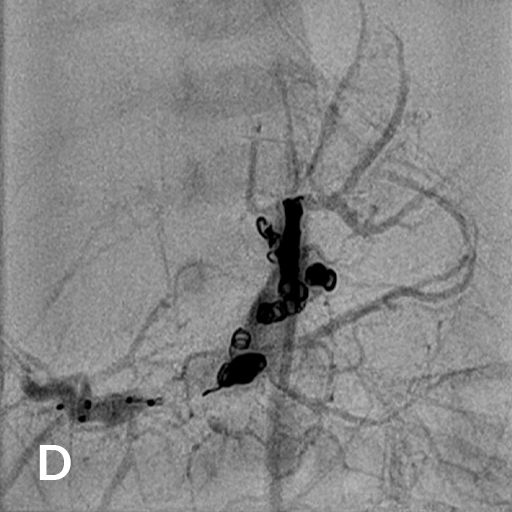

Als Folgen des Pfortaderhochdrucks war die Milz vergrößert (Splenomegalie) und es traten Krampfadern der Speiseröhre (Ösophagusvarizen) auf. Um den Hochdruck zu entlasten wurde ein TIPS angelegt. Dazu wird aus der rechten Lebervene (A) mit einer speziellen Nadel ein Pfortaderast punktiert (B). Anschließend wird die Pfortader mit einem Draht sondiert (C) und die geschaffene Verbindung mit einem Ballon aufgedehnt und anschließend mittels Gefäßstütze (Stent) geschient (D). Durch diese künstliche Verbindung kann das Pfortadersytem deutlich druckentlastet werden.

Reifes Neugeborenes mit Hepatomegalie und Herzinsuffizienz. Das MRT der Leber (A) zeigte ein ausgedehntes kongenitales Hämangiom mit normalem Lebergewebe in den Randbereichen vor allem links. Deutlich gestaute Lebervenen (B) infolge der Rechtsherzbelastung. Die Kontrastmittelinjektion die Arteria hepatica dextra (C) zeigt mehrere arterielle Feeder mit rascher Parenchympassage. Nach interventionellem Verschluss mittels 3 Vascular Plugs und insgesamt 28 Volumen-Coils deutliche Reduktion des Shunt-Flusses im rechten Leberlappen mit noch verbleibenden Hämangiomanteilen links (D).